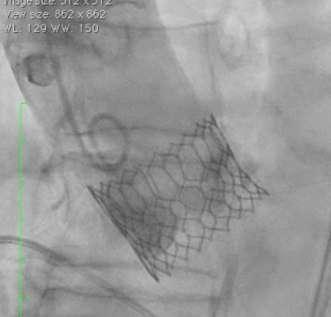

Minimum foot-print in LV (70% Aortic : 30% Ventricular)

Minimal movement across the annulus to locate the THV landing zone

Proximal Balloon Marker

Landing Zone nd2 Dense band 70% 30%

Annular Plane Distal End Towards Ventricle

Mid Balloon Marker

nd2 Light Band

nd2 Dense Band

st1 Light Band

st1 Dense Band

Distal Balloon Marker

Ÿ Shallow deployment of Myval THV with least engagement within LVOT is possible

Ÿ Optimal orthotopic anchorage of Myval THV with marginal LVOT foot-print without risk of THV migration

Ÿ Minimal infra-annular depth ≤3.50mm avoids conduction system interference (thus minimizing the need of new permanent pacemaker dependency)